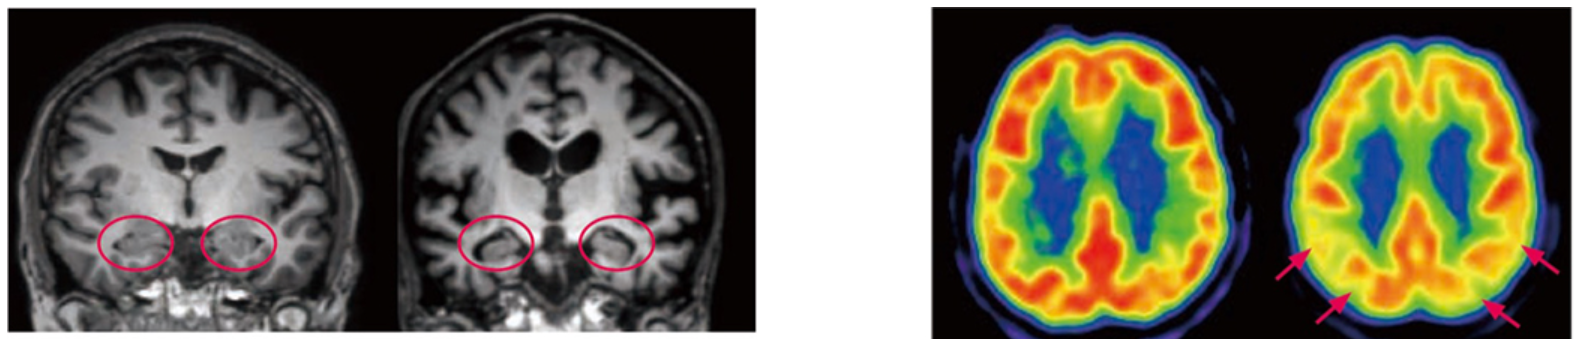

다음으로 뇌혈류SPECT스펙또는 뇌FDG-PET에프디지 애완동물에 의해 뇌의 기능을 진단합니다. 뇌 FDG-PET 쪽이 뇌혈류 SPECT보다 예민하게 기능 이상을 파악할 수 있습니다만, 현재, 아직 건강 보험 적용이 되어 있지 않기 때문에 자유 진료로 뇌 FDG-PET를 실시하는지, 건강 보험 진료로 뇌 혈류 SPECT를 수행합니다. 뇌 혈류 SPECT 및 FDG-PET를 수행하면 알츠하이머 병에서 뇌에정수리 연합야도초렌고우야, 측두 연합야,후부 띠 모양 회고부타이 조카이·쐐기 정면세츠젠부라고 하는 부위에서 혈류나 당 대사가 저하하고 있는 것을 알 수 있습니다(화상 2). 진행하면 전두 연합야의 혈류·대사도 저하해 옵니다. 이러한 소견을 발견함으로써 알츠하이머병을 조기에 발견하거나 다른 치매를 일으키는 질환과 감별합니다.

오른쪽 사진 : 정상자와 알츠하이머병의 뇌 FDG-PET

정상자에서는 뇌의 포도당 대사의 저하는 없습니다만, 알츠하이머병에서는 조기의 단계에서는 두정엽의 대사의 저하가 보입니다(↑)